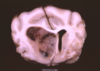

Name & describe the pathologic process.

Hydranencephaly

Near complete or complete absence of the cerebral hemispheres,

leaving fluid-filled sacs formed by the meninges filled with CSF